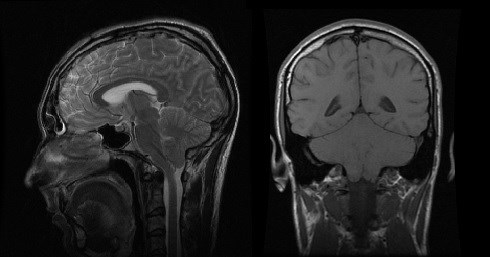

Аномалия Арнольда-Киари: MRI снимки